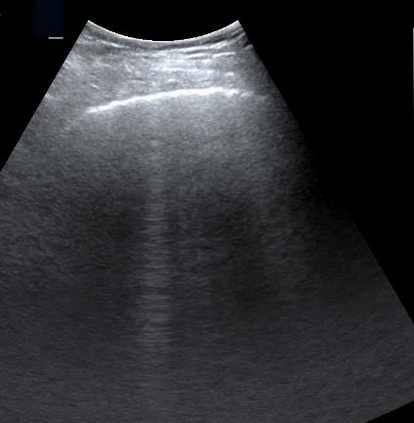

Most deep neural networks (DNNs) based ultrasound (US) medical image analysis models use pretrained backbones (e.g., ImageNet) for better model generalization. However, the domain gap between natural and medical images causes an inevitable performance bottleneck. To alleviate this problem, an US dataset named US-4 is constructed for direct pretraining on the same domain. It contains over 23,000 images from four US video sub-datasets. To learn robust features from US-4, we propose an US semi-supervised contrastive learning method, named USCL, for pretraining. In order to avoid high similarities between negative pairs as well as mine abundant visual features from limited US videos, USCL adopts a sample pair generation method to enrich the feature involved in a single step of contrastive optimization. Extensive experiments on several downstream tasks show the superiority of USCL pretraining against ImageNet pretraining and other state-of-the-art (SOTA) pretraining approaches. In particular, USCL pretrained backbone achieves fine-tuning accuracy of over 94% on POCUS dataset, which is 10% higher than 84% of the ImageNet pretrained model. The source codes of this work are available at https://github.com/983632847/USCL.